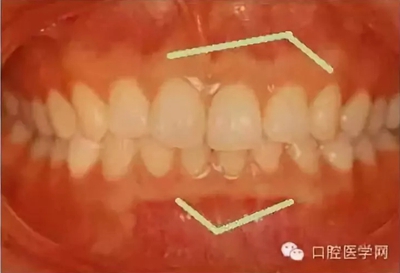

在臨床上我們需要把牙槽骨增生和骨隆突區(qū)分開來,骨隆突是在頜骨上的生理性骨性突起,并不是一個疾病癥狀,也不是疾病的表現(xiàn),比如舌側(cè)骨隆突、上頜骨骨隆突、下頜隆突是在第三磨牙和雙尖牙舌側(cè)的一個生理性突起。

2、對于生理性的骨隆突,一般也不進行治療,在第三磨牙和雙尖牙舌側(cè)牙槽骨的舌側(cè)骨隆突、上頜骨骨隆突、下頜隆突等生理性突起,在進行活動義齒修復的時候應該避讓開這些地方,以免義齒佩戴后產(chǎn)生壓痛。